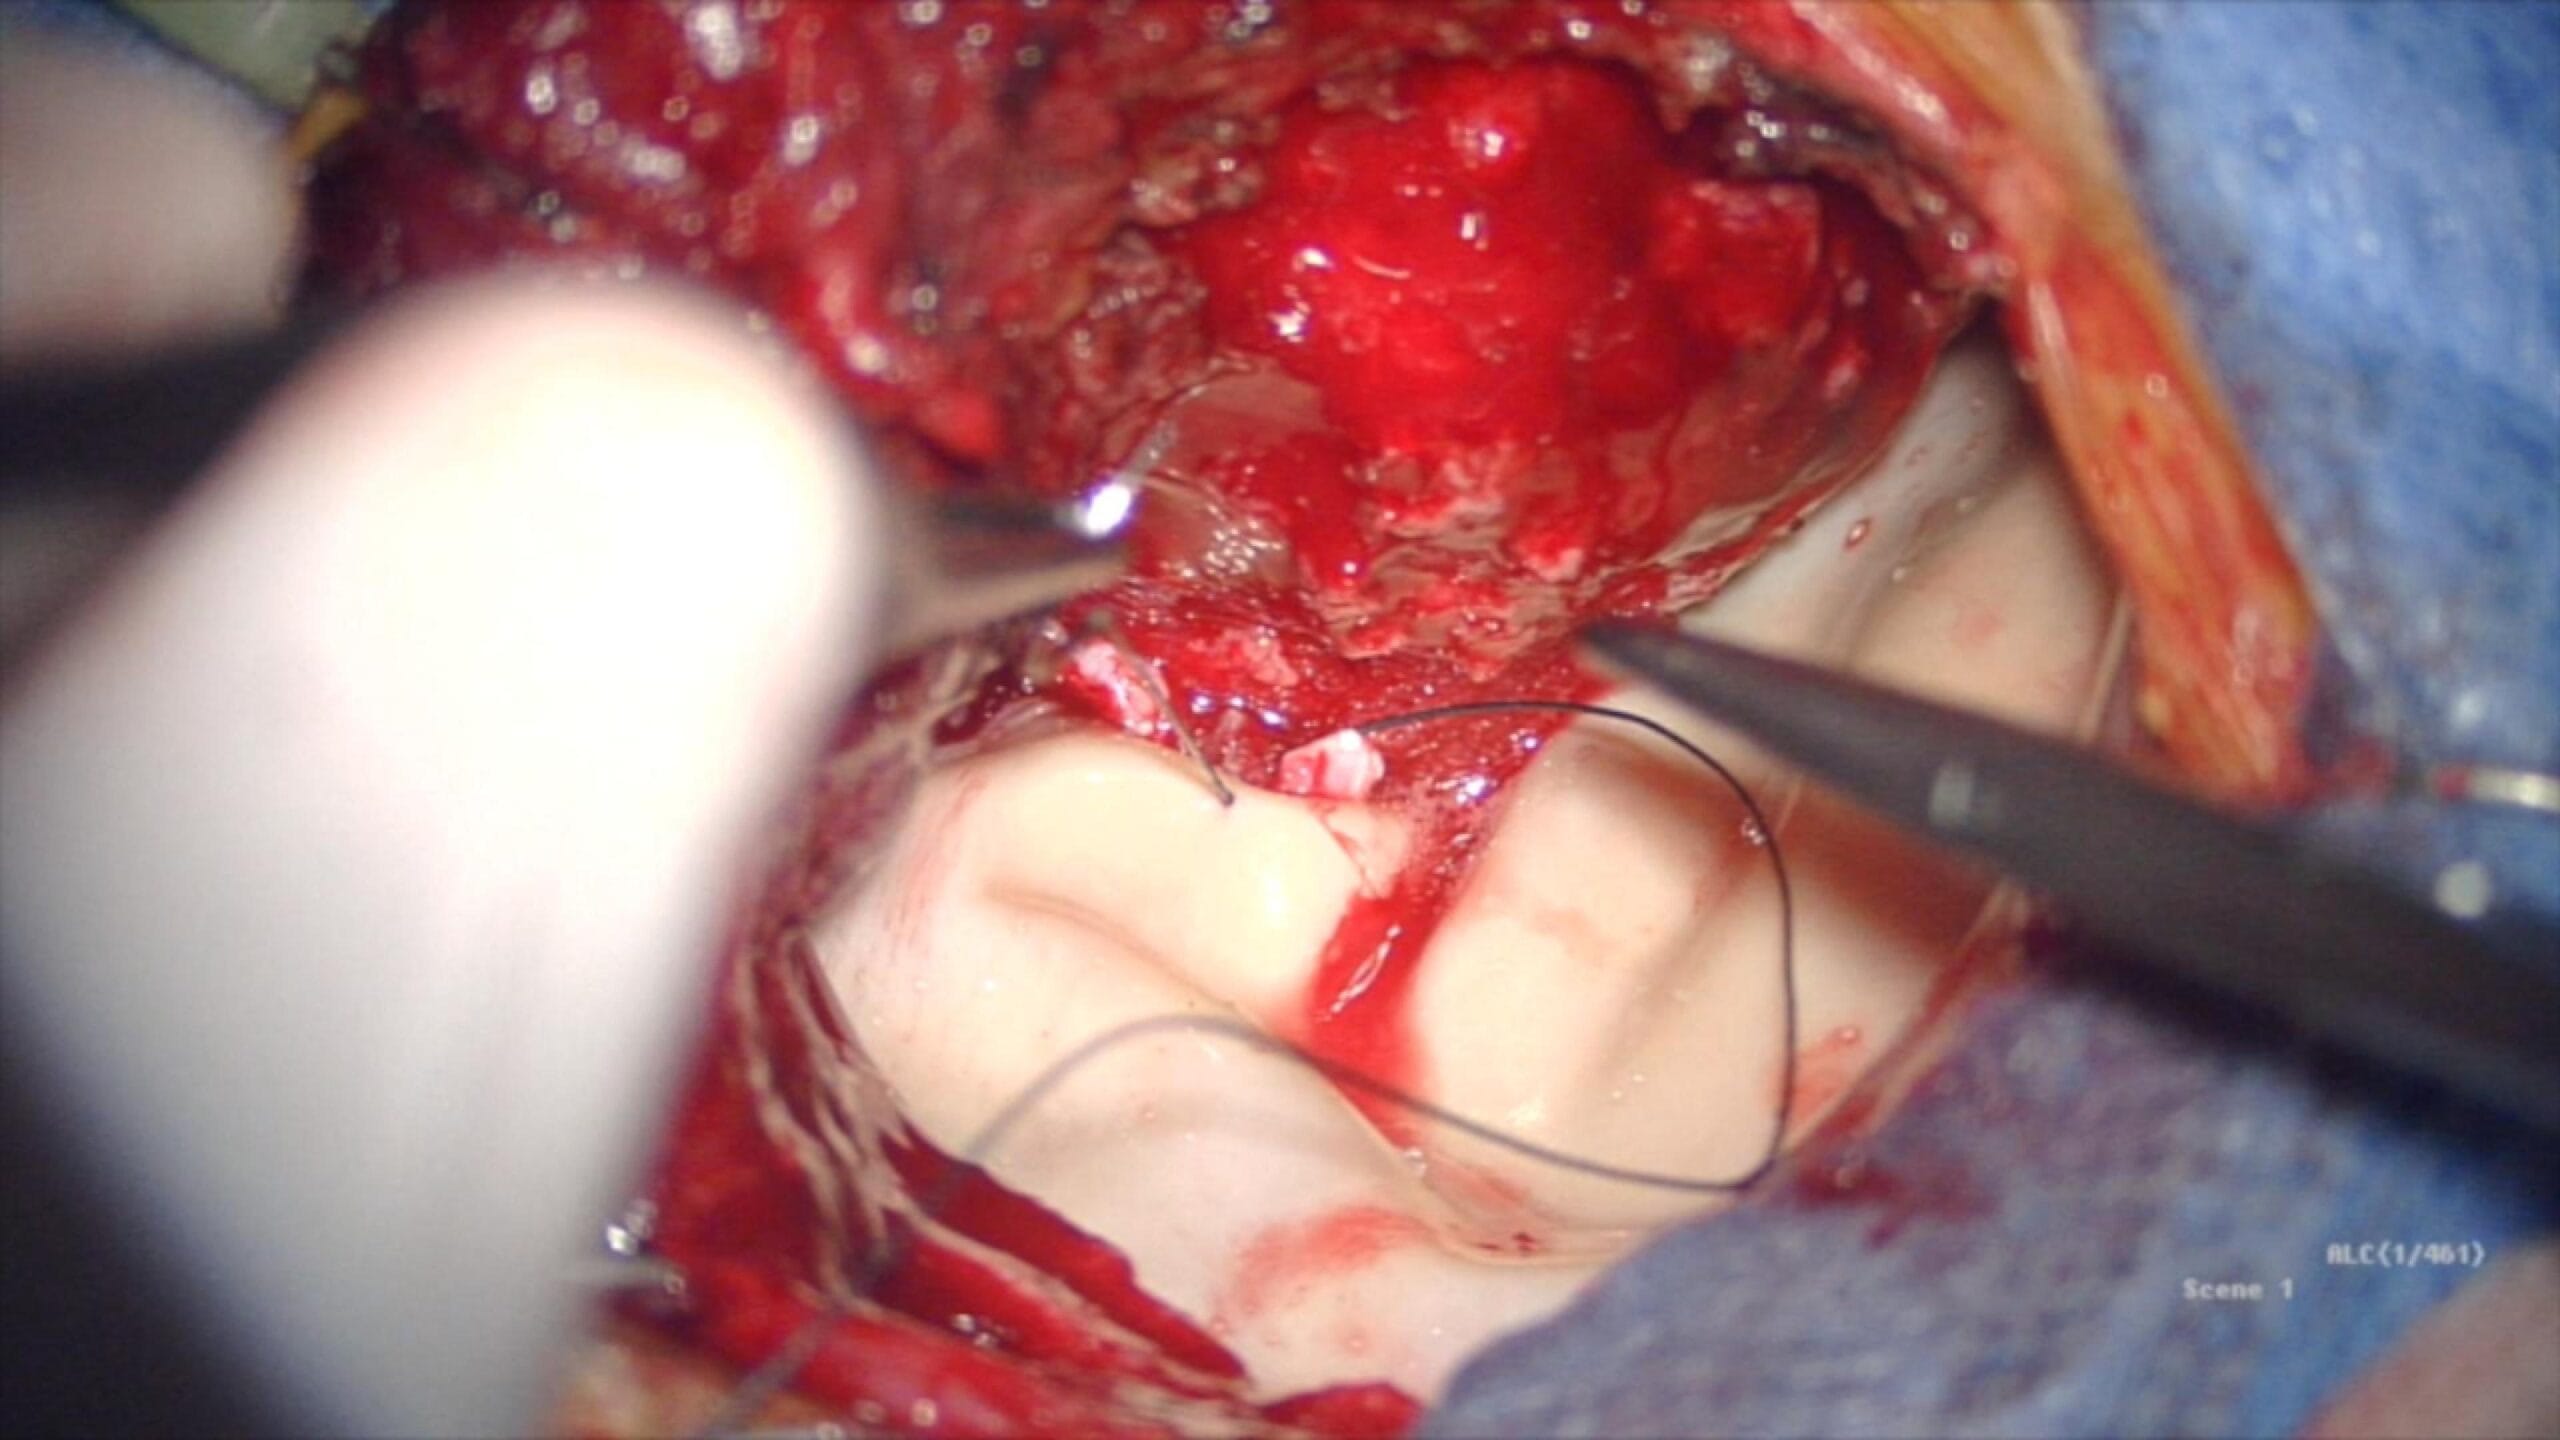

La cirugía culmina con una plástica dural en técnica inlay, suturada sobre duramadre sana, un paso clave para minimizar el riesgo de fístula de LCR en este tipo de resecciones extensas.